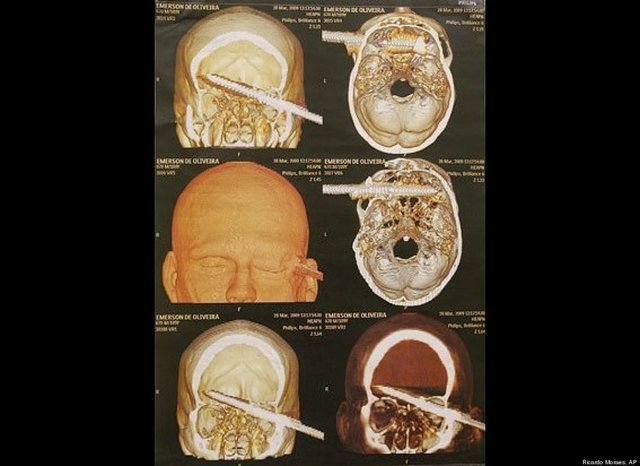

"Özellikle havaalanlarındaki girişlerde iki tür cihazı da görebiliriz. Eşyaların geçirildiği X-Ray cihazında X ışınları kullanılarak görüntüleme yapılır. Çantaların içinde ne olduğu X ışınları ile görüntülenir. Burada uygulanan X ışınlarının eşyalara bir zararı yoktur, birikmez, eşyalarda radyasyon kirliliği yapmaz. Bu cihazların çevresi X ışınlarının insanlara zarar vermemesi için kurşun paravanlarla kaplıdır."